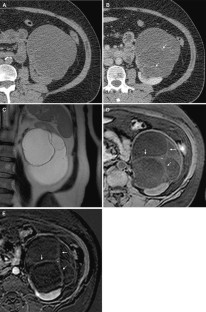

Fig. 4